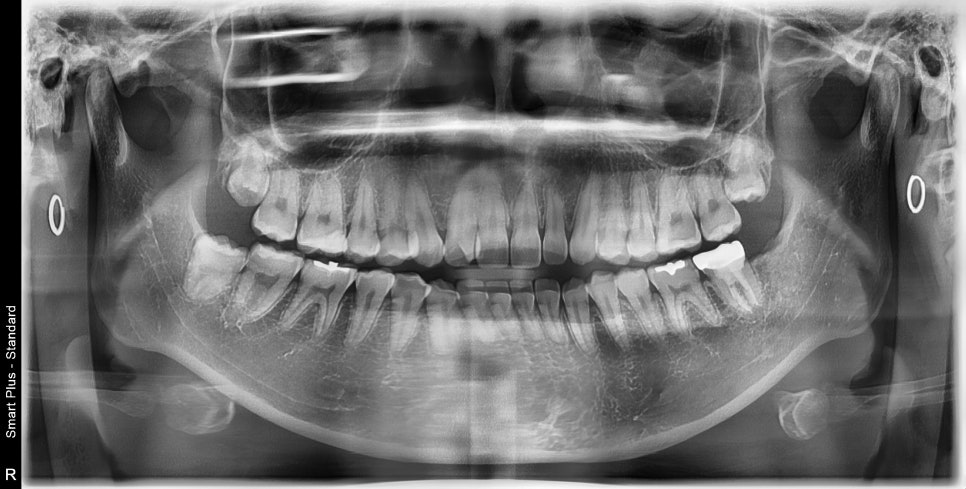

치료 마무리 후

오랜만에 정기검진을 오셨습니다.

신경치료와 보철치료까지 깔끔하게 마무리되었고

그 옆의 사랑니 뺀 곳은 흔적을 찾아볼 수 없을 정도로

뼈가 다 차있는 것을 볼 수 있습니다.

너무 깊이 매복이 되어있어서

발치 당시에는 통증이 좀 있으셨었는데

이렇게 회복된 것을 보니

치료를 잘 받아주신 것에 대해 감사했습니다.